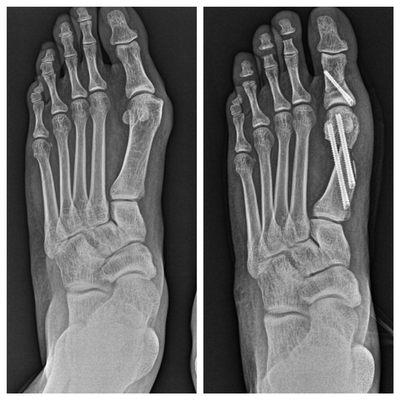

The doctors and staff at Lake Ridge and Stafford Foot & Ankle Centers are dedicated to providing state-of-the-art medical care and a comfortable, caring office environment to patients of all ages. With over 100 years of combined experience, the team of highly trained, board-certified foot and ankle surgeons is frequently recommended by other physicians in the northern Virginia area. Committed to maintaining a modern, up-to-date practice, the doctors offer total ankle replacement surgery, Charcot’s diabetic foot and ankle reconstruction surgery, infections and wound care, pediatric surgical care, bunion correction, and sports medicine.